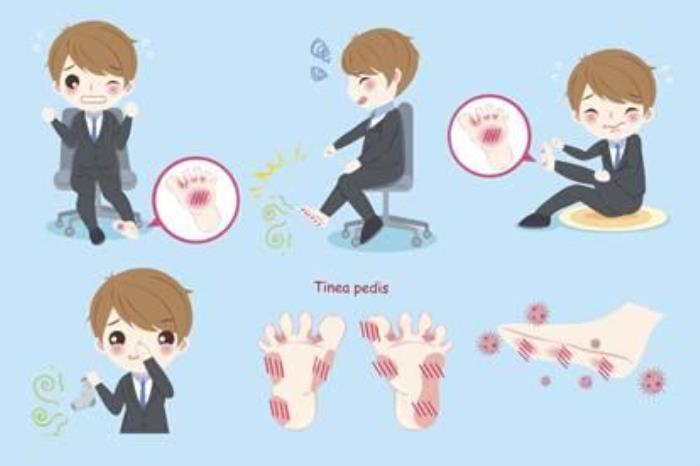

(央视财经《职场健康课》)您有过双脚瘙痒难忍的经历吗?您知道有一种脚部的皮肤感染如果处理不当会侵犯全身、甚至还会导致可怕的并发症吗?然而最让人毛骨悚然的就是它的高传染性,也许只是我们每天生活中最简单的接触,就有可能被传染!这个不起眼的小毛病什么情况下会变成可怕的全身性疾病?日常生活中有哪些误区会让我们无意中中招?这种难缠的小毛病是否能治愈呢?

脚气学名为足癣,我们俗称脚气、“香港脚”,简单的讲,它是由致病真菌感染引起的一种足部皮肤病。临床表现为皮肤起水疱、脱皮或皮肤发白湿软,也可出现糜烂或皮肤增厚、粗糙、开裂,奇痒无比。

脚气最典型的一个症状就是瘙痒难忍。其实,不同的类型会有各种不同的表现形态。